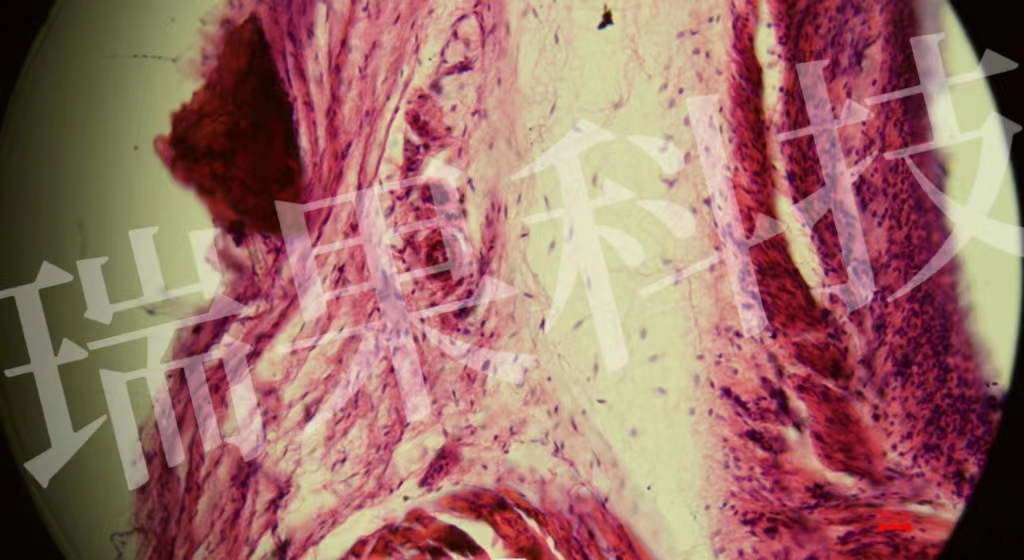

HE染色:苏木精 - 伊红染色法 ( hematoxylin-eosin staining ) ,简称HE染色法 ,石蜡切片技术里常用的染色法之一 。苏木精染液为碱性 ,主要使细胞核内的染色质与胞质内的核酸着紫蓝色 ;伊红为酸性染料 ,主要使细

HE染色:苏木精 - 伊红染色法 ( hematoxylin-eosin staining ) ,简称HE染色法 ,石蜡切片技术里常用的染色法之一 。染液为碱性 ,主要使细胞核内的染色质与胞质内的核酸着紫蓝色 ;伊红为酸性染料 ,主要使细胞质和中的成分着红色 。HE染色法是组织学、、病理学教学与科研中最基本、使用最广泛的技术方法。

气管